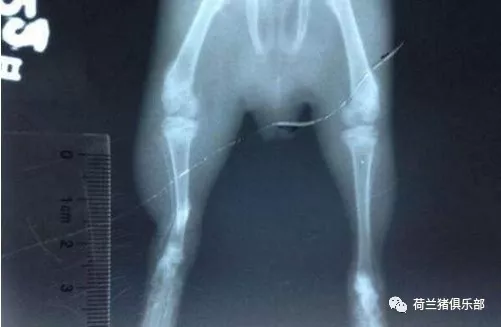

3、有一些骨折或者輕微的骨裂,用肉眼看或者手摸判斷不出來的,這個時候就要用寵物用的X光機來拍一張X光照片來確定一下是不是骨折了。如果真的骨折的話,X光片上能看到明顯的骨折痕跡。拍X光片也是最好的判斷是不是骨折的方法了。